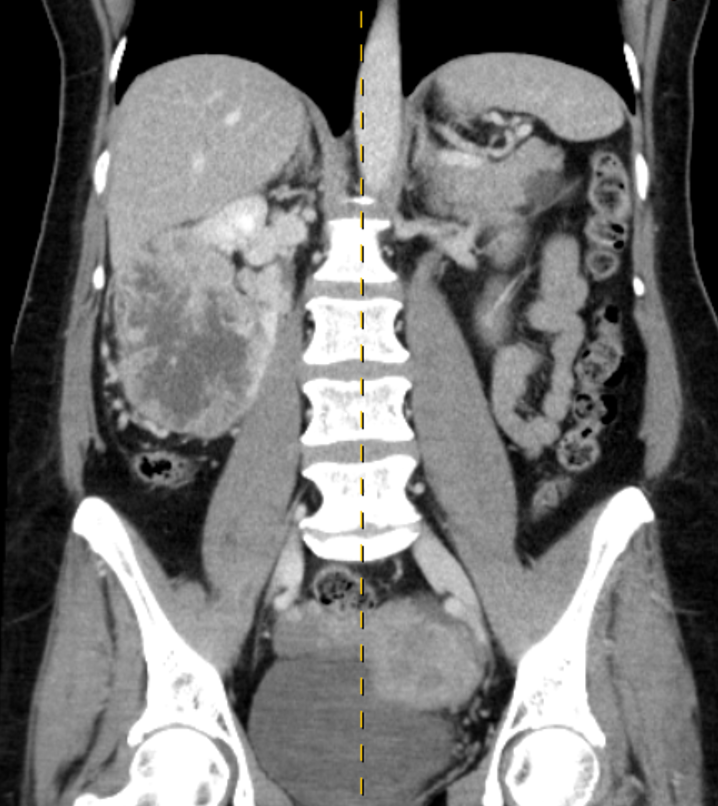

CT Chest/ Abdomen / Pelvis

Lung / bowel / renal primary

Lung metastasis

Lung cancer Renal cell cancer